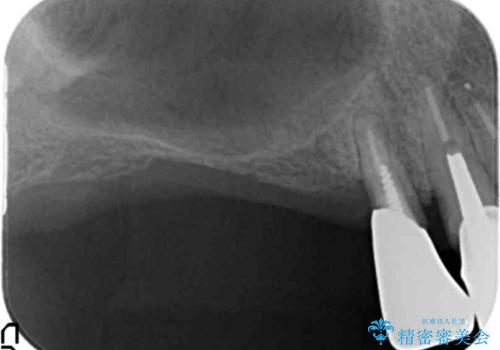

- 歯周病で失った奥歯や、グラグラしている歯の治療を希望され来院されました。

残すことのできない歯を抜去したのち、骨を造成し安定した環境下で長期的な予後を期待できるインプラント治療を計画します。